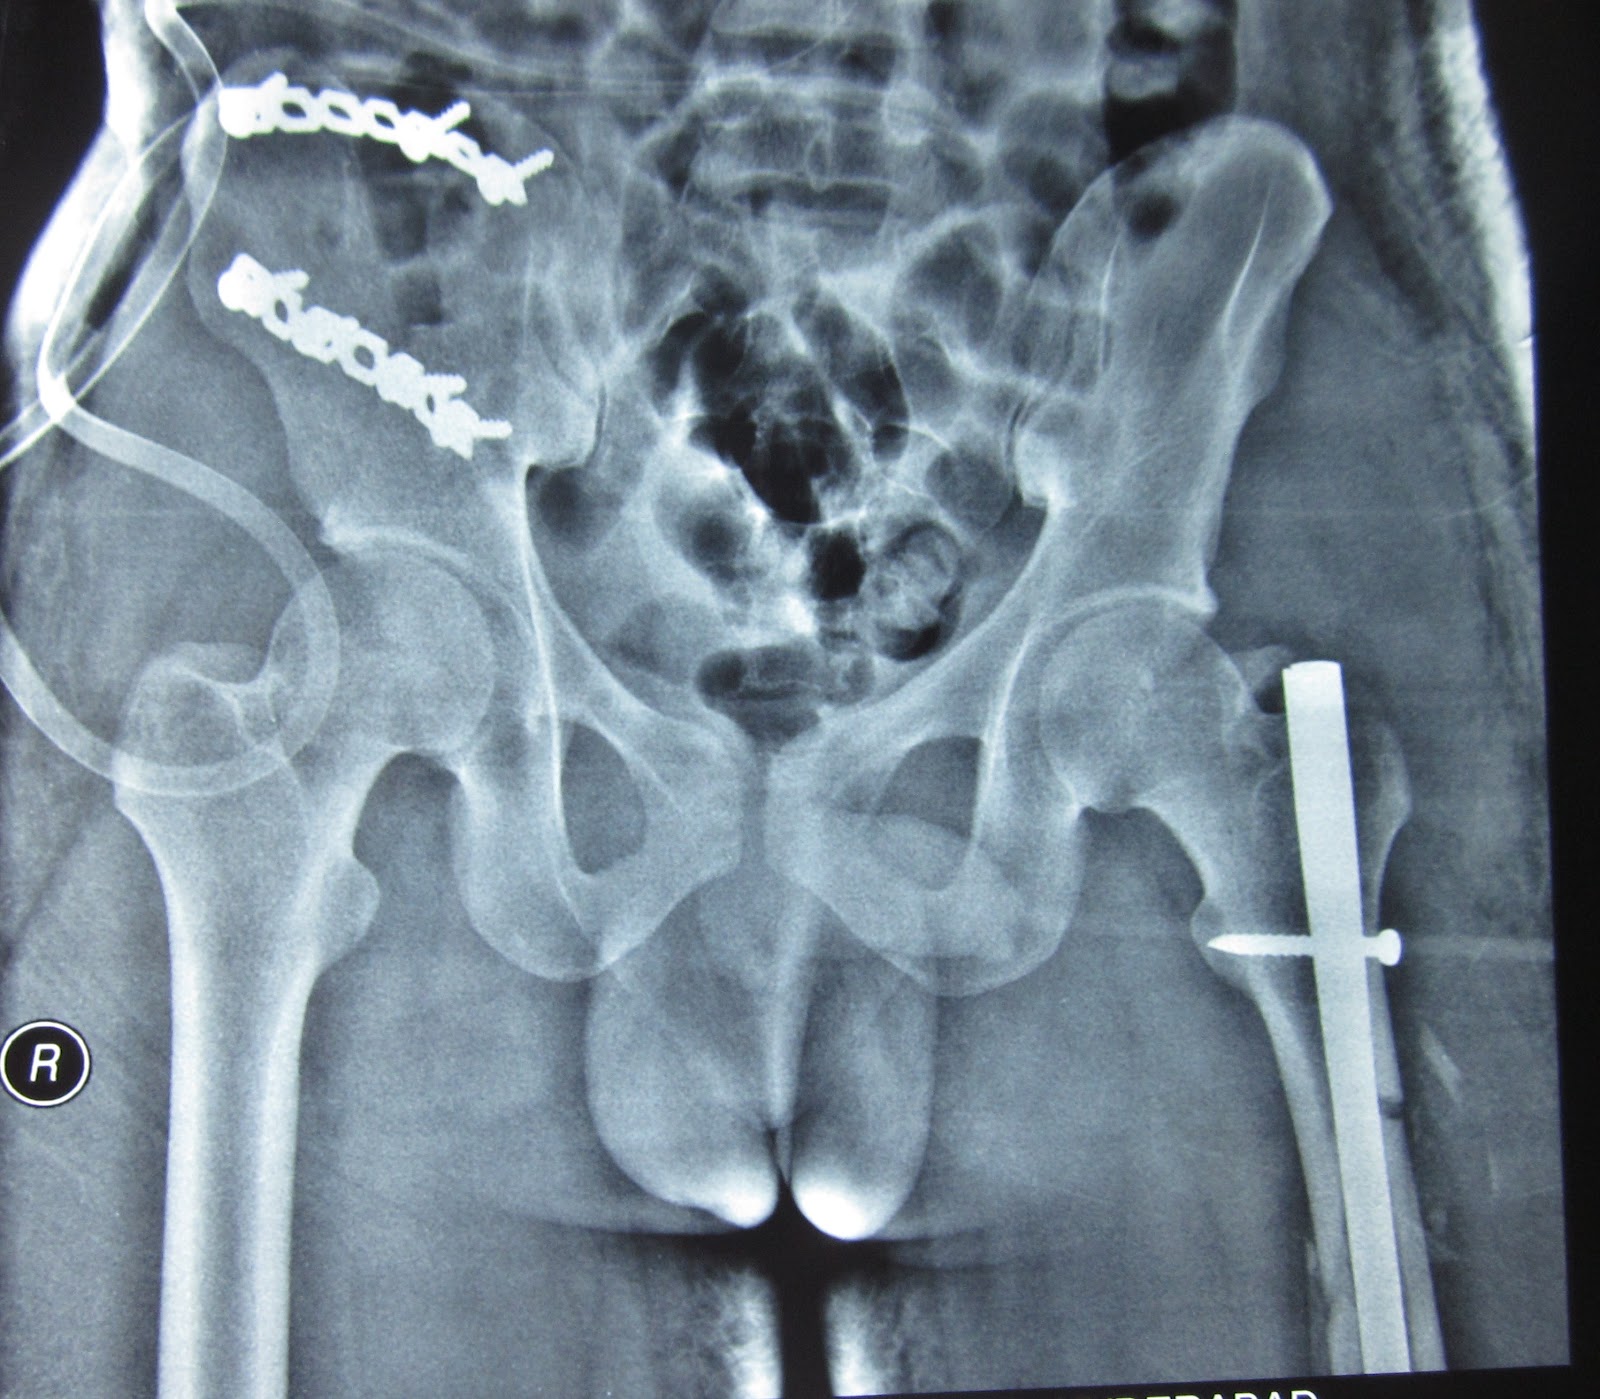

CRUSH INJURY OPEN PELVIC FRACTURE, ASSOCIATED FEMUR FRACTURE ON Is A Crush Injury A Fracture Crush syndrome is the systemic manifestation of severe, traumatic muscle injury. A crush injury occurs when force or pressure is put on a body part. This type of injury most often happens when part of the body is squeezed. Crush injuries of the hand involve damage to multiple structures within the hand, loss of tissue, devascularisation and possibly amputation of.. Is A Crush Injury A Fracture.